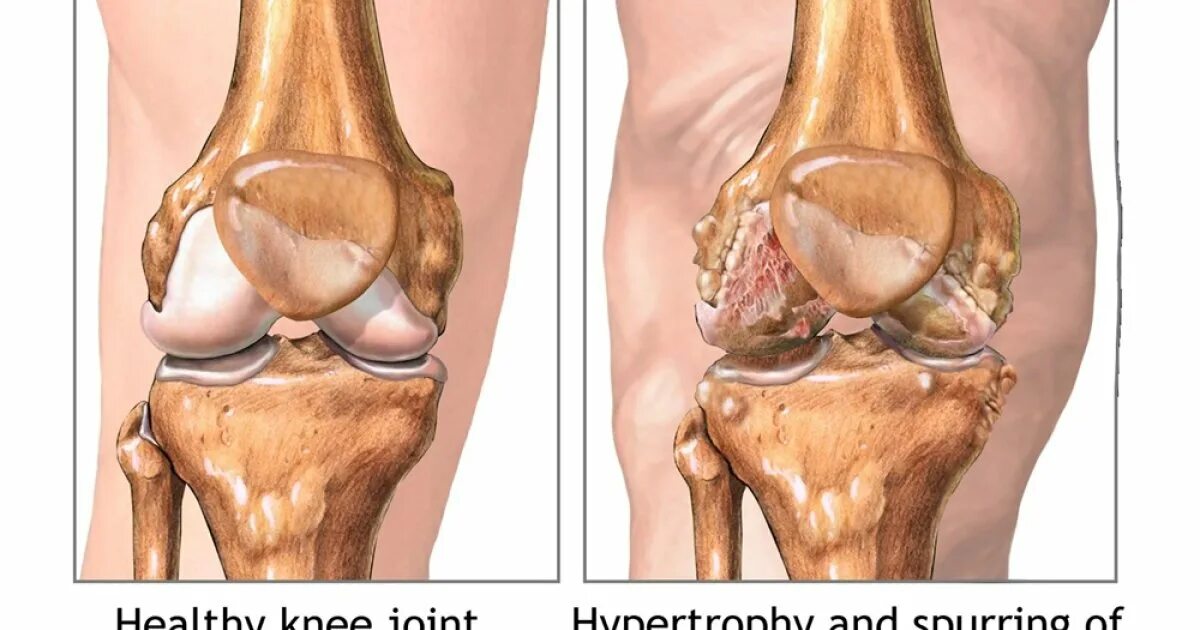

Деформирующий остеоартроз коленного сустава 1